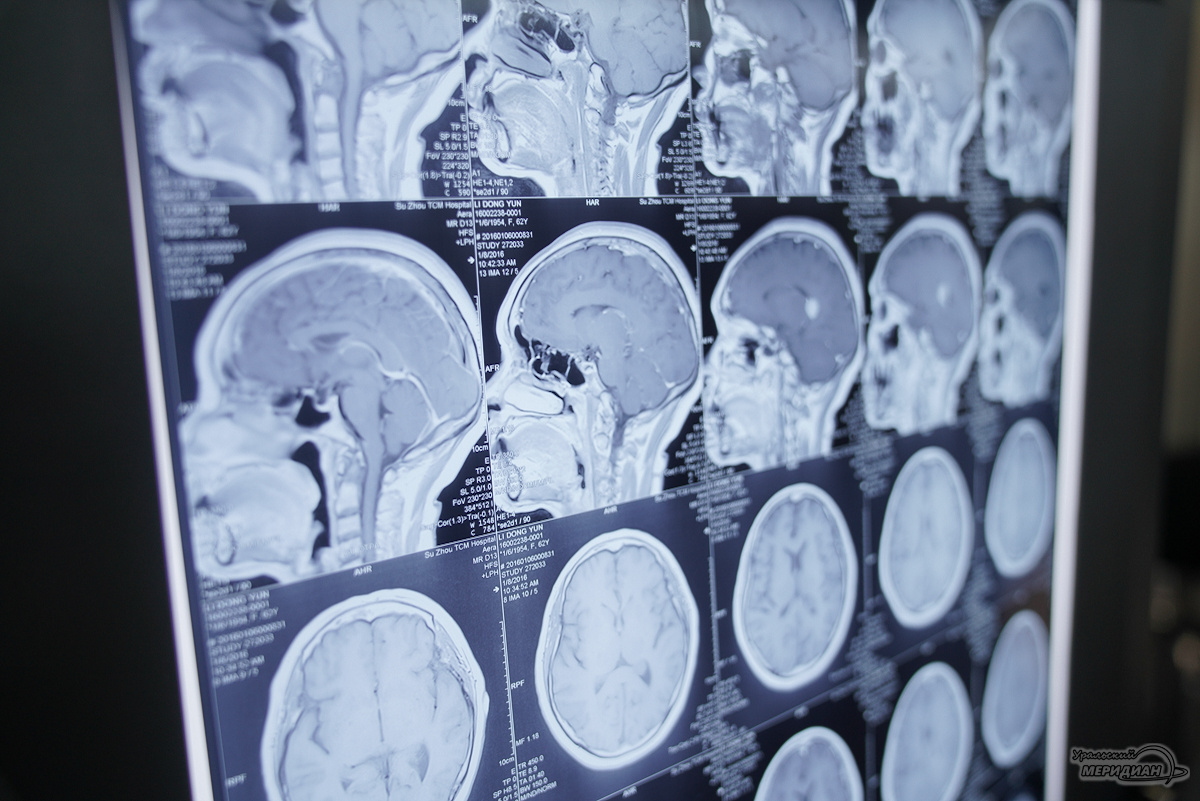

Инцидент произошёл в Серове, где стрела крана нанесла мужчине серьёзную травму — расколола череп. Пациент поступил в критическом состоянии в единственное на севере области стационарное отделение скорой медицинской помощи при Серовской городской больнице. Быстрая диагностика с помощью высокоточного компьютерного томографа позволила выявить расположение костных отломков в мозге, среди которых один угрожал жизни пациента.

Специалисты из Екатеринбурга в ходе телеконсультации рекомендовали экстренную перегоспитализацию пациента в межмуниципальный медицинский центр, и мужчину доставили в Городскую больницу №1 Нижнего Тагила. Там нейрохирург Дмитрий Неволин, анестезиолог-реаниматолог Аслам Абдуев и операционная медсестра Нина Дмитриева провели сложную операцию — удалили костные отломки, гематомы и восстановили целостность твёрдой мозговой оболочки.